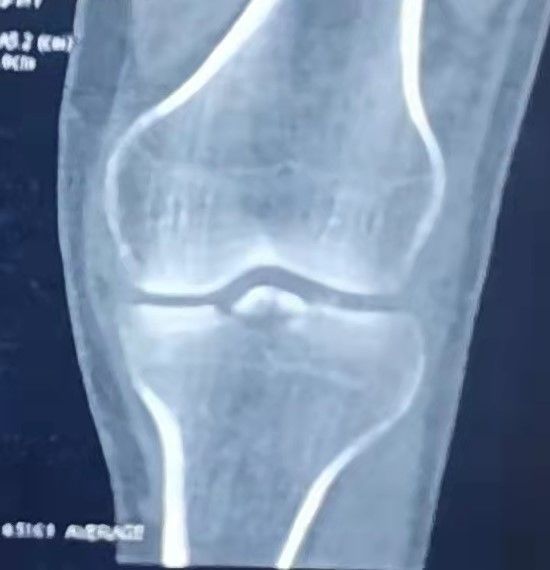

左膝正侧位DR:左膝前交叉韧带胫骨止点撕脱骨折,内侧胫骨平台骨折,均未见明显移位。

左膝CT

初步诊断:1、左膝ACL胫骨止点撕脱骨折 2、左膝胫骨平台骨折(Schatzker Ⅰ型) 3、左膝关节积液